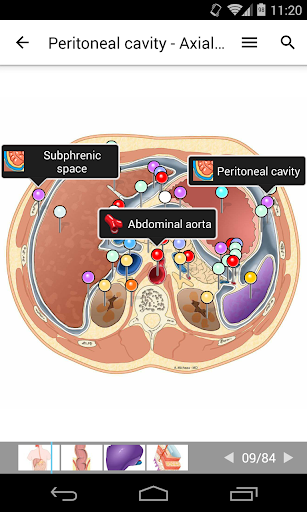

e-Anatomy tiene más de 26 000 imágenes que contienen series de imágenes en vistas axiales, coronales y sagitales, así como radiografías, angiografías, imágenes de disección, gráficos anatómicos e ilustraciones. Todas las imágenes médicas fueron etiquetadas cuidadosamente, más de 967 000 etiquetas disponibles en 12 idiomas, incluida la Terminologia Anatomica latina.

- Desplácese por los conjuntos de imágenes arrastrando el dedo

- Acerque y aleje el zoom

- Toque las etiquetas para mostrar las estructuras anatómicas

- Seleccione las etiquetas anatómicas por categoría